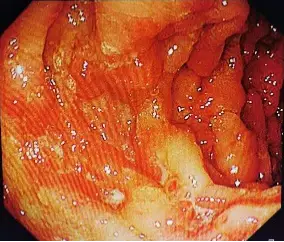

每次检查完,医生都会耐心地解释X线片上的那些黑影和白影,告诉我哪里发炎了,哪里有溃疡。